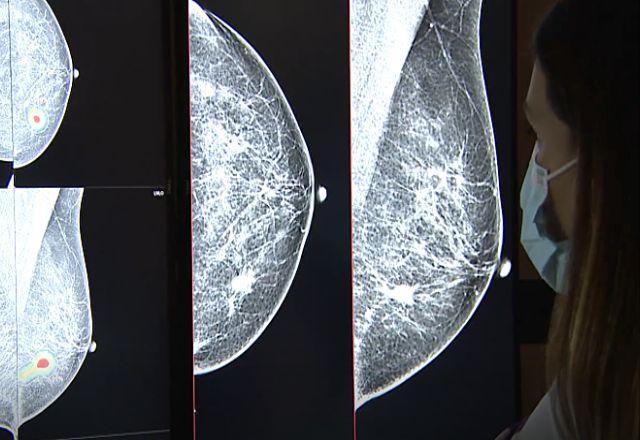

No centro de referência de São Paulo, os médicos contam, agora, além da própria experiência, com um segundo olhar para uma avaliação ainda mais precoce da doença: o olhar da inteligência artificial. As mamografias são submetidas a um programa de computador que aponta, em segundos, lesões suspeitas.

"Ela indica para a gente que nessa mesma região aqui existe algo errado. Ele circula com um mapa de calor, mostrando que a gente tem que dar uma maior atenção para uma determinada região", explica a coordenadora médica do centro de Imaginologia Mamária da BP, Carla Benetti.

O programa aprende com milhares de exames já realizados, inseridos no sistema, criando padrões, que servem de referência, e atinge uma precisão que o olho médico não consegue.

"Nódulos muito muito pequenos, calcificações muito discretas... casos de mamas densas, às vezes, a sensibilidade é menor, e daí a inteligência artificial pode ajudar a identificar lesões que poderiam passar despercebidas a olhos humanos", acrescenta a especialista.